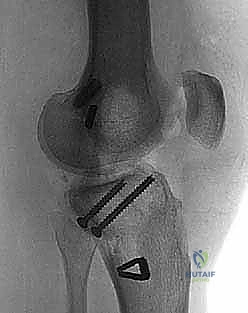

Operative Techniques in Orthopaedic Surgery